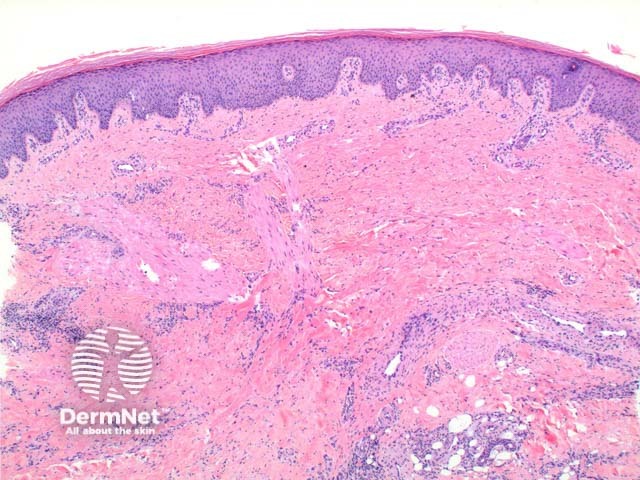

Scanning power view of necrobiosis lipoidica demonstrates a layered inflammatory process and alternating zones of necrobiosis involving the full thickness of the dermis (Figure 1). The changes tend to become more pronounced deeper in the dermis and may extend into the septal panniculus (Figures 2 and 3). The areas of necrobiosis are poorly defined and run into each other with broad foci of inflammatory infiltrate intervening (Figure 4). This may form a stacked ‘lasagne’ type appearance. A variable histiocytic infiltrate with multinucleated giant cells surrounds these areas. The accompanying inflammatory infiltrate is predominantly lymphocytic with plasma cells and occasional eosinophils (Figure 5). As lesions age an increasing degree of dermal fibrosis is seen.

Figure 1